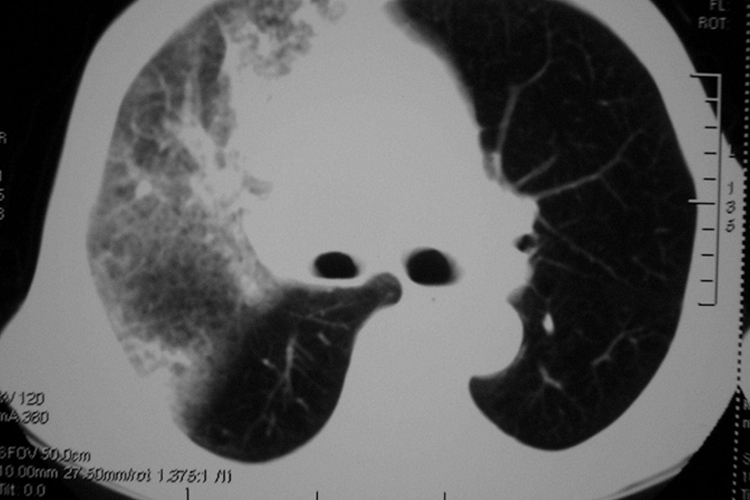

肺出血CT检查,主要表现为广泛的斑片状阴影,大小不一,密度均匀,有时可有支气管充气征。肺血管存在出血淤血影,比如两肺门血管影增多,两肺或呈较粗网状影。同时心影轻至中度增大,以左心室增大较为明显,严重者心胸比>0.6。如果是大量出血时,两肺透亮度明显降低或呈“白肺”征,或可见到原发性肺部病变。另外临床常出现皮肤苍白、呼吸暂停、呼吸困难,甚至鼻腔、口腔流出或喷出血性液体等症状、